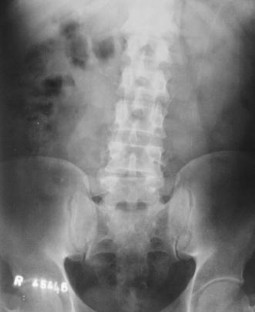

We report a case of L4–L5 traumatic anterolisthesis. The patient was treated surgically 4 months after the injury. His radiological and operative findings showed L4 inferior facet tip fracture, L4–L5 anterior displacement and left L4–L5 foraminal disc protrusion. Decompression, reduction with L3, L4, L5 pedicular screw fixation, L4–L5 disc excision and interbody cage insertion with autologous bone grafts were done. Flexion type injury was thought to be the probable mechanism.

Fig. 2